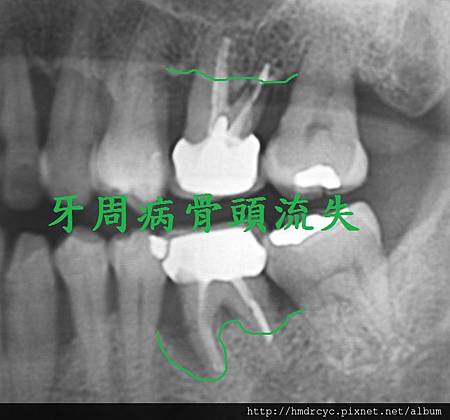

2. 牙周病與骨頭破壞

牙周病不管在假牙或自然牙齒

都必須X光來診斷嚴重程度

而牙周病最可怕的部分就是造成骨頭破壞

有時候外表看起來不錯的牙齒

其實裡面骨頭以經破壞嚴重甚至造成動搖

嚴重者骨頭以經完全破壞

牙齒失去支撐 就會浮起來

這時就只能考慮拔除

骨頭破壞後原本骨頭位置被發炎的肉取代

甚至形成膿包